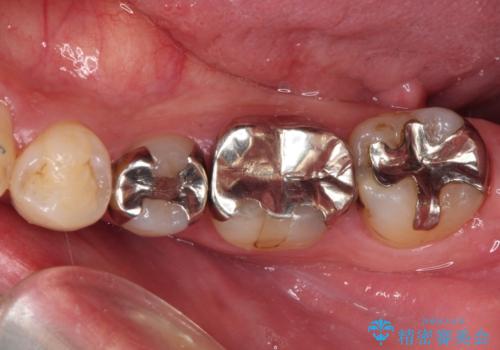

奥歯には目立つ銀歯が多くあるので、矯正治療後には下顎の銀歯をセラミッククラウンやセラミックインレーにより、補綴・修復治療することとしました。